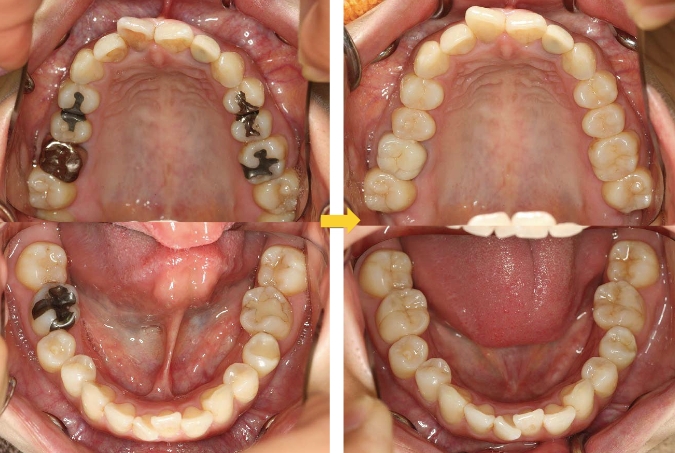

• CASE5.全顎治療

• point.png

• レジン治療:10本 / 治療期間:3ヶ月

• case5.png